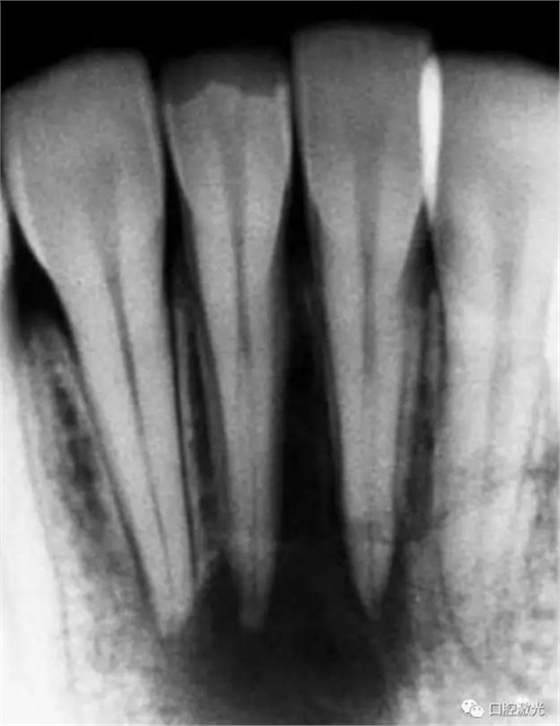

41 治療前X光片

激光治療中

6個月后治療效果